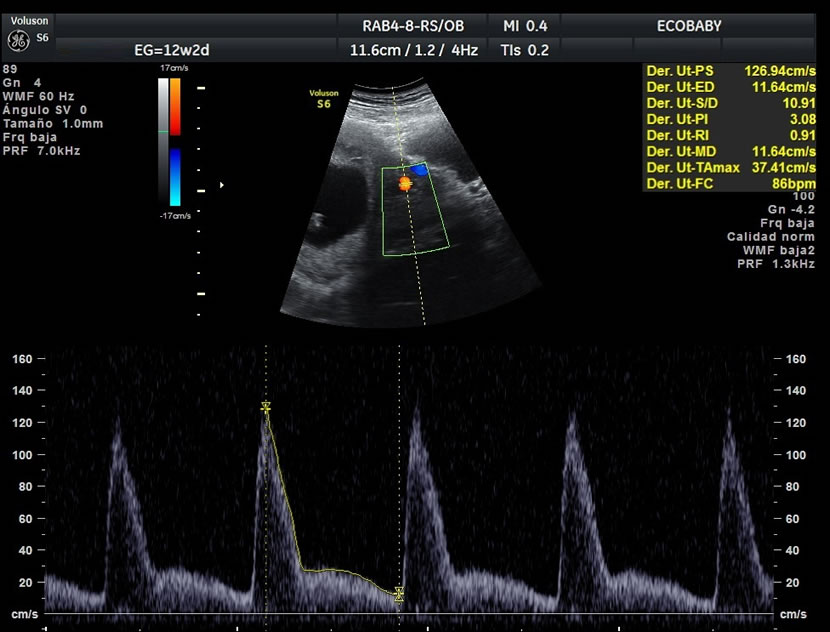

> Para medir la frecuencia cardiaca fetal

> Para estudiar el flujo a través de la válvula tricúspide del corazón fetal y el ductus venoso